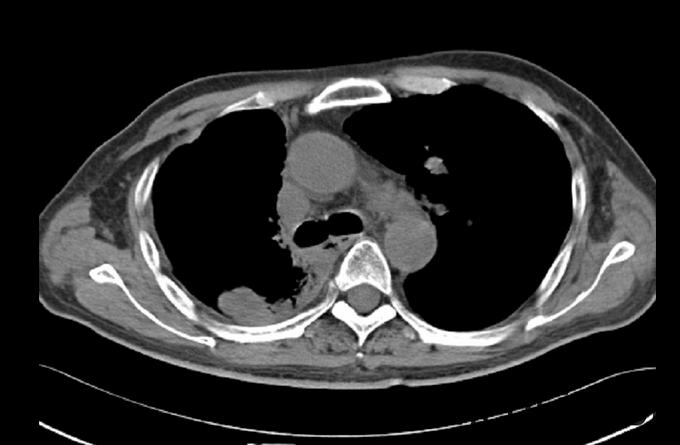

神清,精神可,生命体征平稳,双侧瞳孔等大等圆,直径约3mm,对光反射灵敏,动眼自主,额纹对称,嘴角伸舌无歪斜。颈软,心肺听诊无殊,右侧侧胸部可见长约12cm手术疤痕,愈合可,腹平软,肝脾肋下未及,四肢感觉对称,活动自主,肌力5级,肌张力不高,病理征阴性。 辅助检查: (2015-08-06 13:58)行放射检查(胸部)检查提示:肺癌术后改变,两肺弥漫性结节,转移瘤首先考虑;右侧胸腔积液。

初步诊断:1.颅内转移性肿瘤 2.右肺腺癌术后,两肺转移。入院后完善相关检查:(2015-10-01 18:34)(急诊)血常规(血液):白细胞计数16.6×10^9/L↑、中性粒细胞百分比95.4%↑、(2015-10-01 19:19)(急诊)降钙素原(血液):C-反应蛋白217.5mg/L↑、癌胚抗原248.9ng/mL↑、癌抗原199354.0U/mL↑、癌抗原12556.0U/mL↑、癌抗原24277.8U/mL↑,(2015-10-05 14:04)行CT(胸部)检查提示:肺癌术后改变,两肺多发结节,考虑转移,较前(2014.05.05)增大、增多。入院后予邦达抗感染、甲泼尼龙40mg bid静滴减轻炎症反应,冸托拉唑40mg qd护胃,奥拉西坦4g qd修复脑神经,经治疗后患者病情好转,目前病情稳定,今予出院。